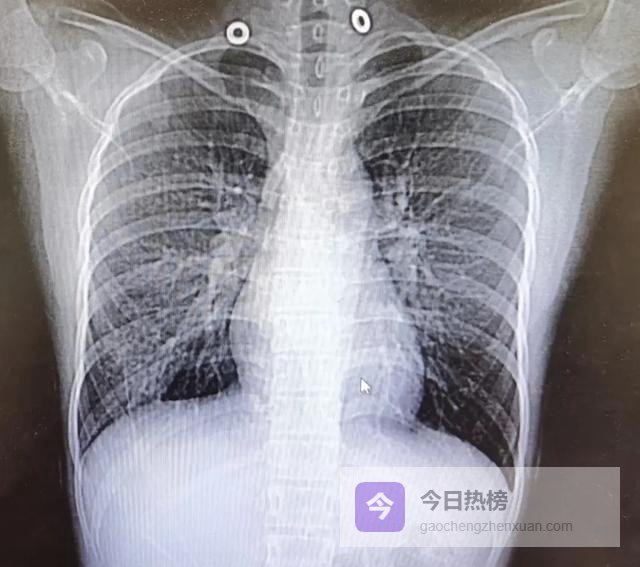

医生在评估肺癌风险时,并非简单地看有没有“结节”,而是聚焦于几个高度提示性的影像学特征。

当一份CT报告中完全未出现“磨玻璃密度”、“分叶征”、“毛刺征”、“胸膜凹陷”或“血管集束征”等描述时,临床普遍认为其恶性可能性极低。

肺组织本应如轻盈的海绵,充满空气,通透均匀。一旦出现异常密度,意味着局部结构被“填充”或“破坏”。

“磨玻璃影”(Ground-GlassOpacity,GGO)之所以令人关注,是因为它往往代表肺泡壁增厚、细胞异常增生或早期腺癌原位阶段。

此时肿瘤细胞尚未完全取代肺泡结构,因此仍能透光,呈现出朦胧的“磨砂玻璃”样外观。若这种影子稳定存在超过3个月,尤其直径大于8毫米,医生会建议密切随访。

而“实性结节”本身并不可怕,多数是良性肉芽肿或陈旧瘢痕。真正让医生皱眉的是它的“长相”。一个边缘光滑、边界清晰的圆形小点,很可能是炎症愈合后的遗迹;

但若边缘呈“分叶状”——就像一颗不规则的土豆,表面凹凸起伏,这往往是肿瘤生长速度不均所致。

更值得警惕的是“毛刺征”,即结节周围放射出细短的线条,如同海胆的刺,这是肿瘤向周围组织浸润性生长的直接证据。

“胸膜凹陷征”描述的是结节牵拉邻近胸膜形成的小坑,仿佛用手指轻轻按压气球表面;“血管集束征”则指多条血管像被磁石吸引般汇聚向结节。

这两者都是肿瘤刺激局部纤维收缩和新生血管生成的结果。这些特征单独出现或许尚可观察,但若组合出现,恶性概率将显著上升。